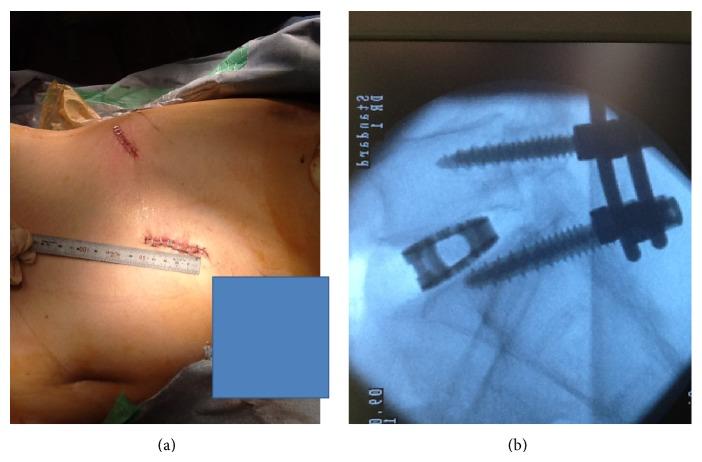

Extreme lateral interbody fusion (XLIF) has been widely used for minimally invasive anterior lumbar interbody fusion (ALIF), but an approach to L5-S1 is difficult because of the iliac crest. In the current study, we present 2 cases using minimally invasive oblique lateral interbody fusion (OLIF) of L5-S1. The patients showed foraminal stenosis between L5 and S1 and severe low back and leg pain. The patients were placed in a lateral decubitus position and underwent OLIF surgery (using a cage and bone graft from the iliac crest) without posterior decompression. Posterior screws were used in the patients. Pain scores significantly improved after surgery. There was no spinal nerve, major vessel, peritoneal, or urinary injury. OLIF surgery was minimally invasive and produced good surgical results without complications.

极外侧椎间融合术(XLIF)已广泛应用于微创前路腰椎椎间融合术(ALIF),但由于髂嵴的存在,L5-S1节段的手术入路较为困难。在本研究中,我们展示了2例采用L5-S1微创斜外侧椎间融合术(OLIF)的病例。患者表现为L5和S1之间的椎间孔狭窄以及严重的腰腿痛。患者取侧卧位,接受OLIF手术(使用椎间融合器和取自髂嵴的骨移植),未进行后路减压。患者使用了后路螺钉。术后疼痛评分显著改善。未发生脊神经、大血管、腹膜或泌尿系统损伤。OLIF手术具有微创性,手术效果良好,无并发症发生。